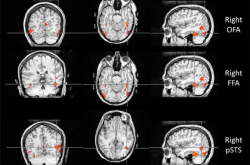

你能记住多少张脸?研究发现,人类平均能记住约 5000 张面孔(波动范围约为1000~10000),这一能力在自然界中无可比拟。而大多数动物识别同类主要依赖气味或声音,而不是脸。一些高度社会化的家畜,比如绵羊,在经过特殊训练后能记住大约 50 张羊脸,仅有人类的百分之一。除了人类以外的其他灵长类,识脸能力在动物界也属于佼佼者,但数量多在数十到上百张之间,目前仍缺乏确切的上限数据。为什么人类拥有如此出众的“认脸”能力呢?人类拥有与生俱来的“认脸系统”这是因为人脑中存在一套专门“...